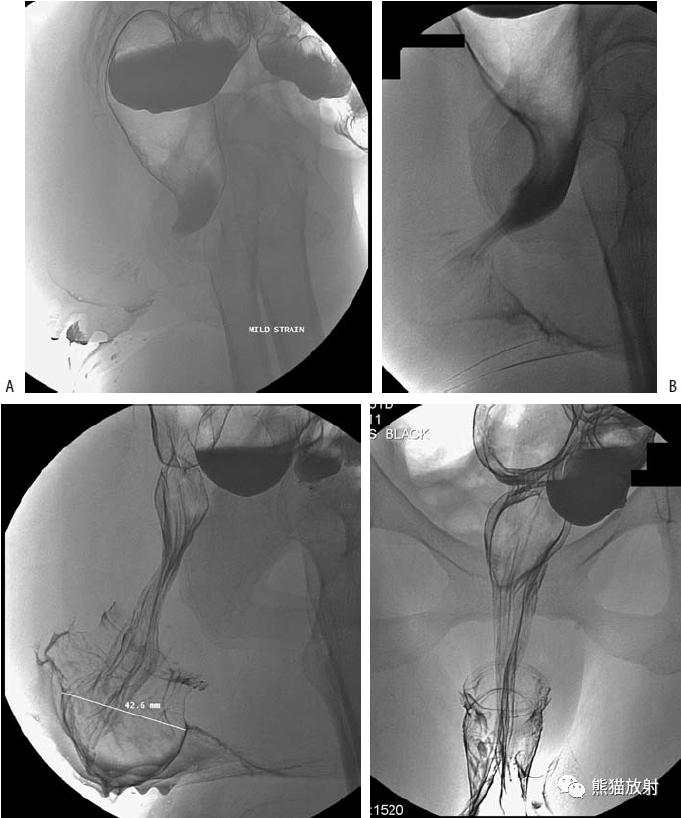

盲肠扭转。X线摄片显示中腹部肠管明显扩张(箭头)。钡餐检查示升结肠扭曲部位可见特征性的鸟嘴征(箭头)。

乙状结肠扭转。消化道造影侧视图可见乙状结肠局部走行扭曲(箭头)。